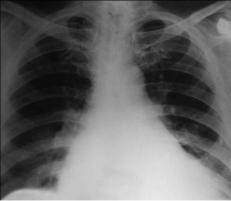

Рентгенологическое исследование.

Увеличение левого предсердия, выбухание третьей дуги на левом контуре сердца, а также левого желудочка (закругление четвертой дуги на левом контуре сердца, уменьшение ретрокардиального пространства) (рис.

8-1).

Рис. 8-1. Недостаточность митрального клапана.

В случае развития легочной гипертензии отмечаются расширение корней легких с нечеткими контурами, сосудами, прослеживаемыми до периферии легочных полей. Увеличение правого желудочка как реакция на повышение давления в легочной артерии выражено обычно нерезко, так как легочная гипертензия при данном пороке не достигает больших степеней.